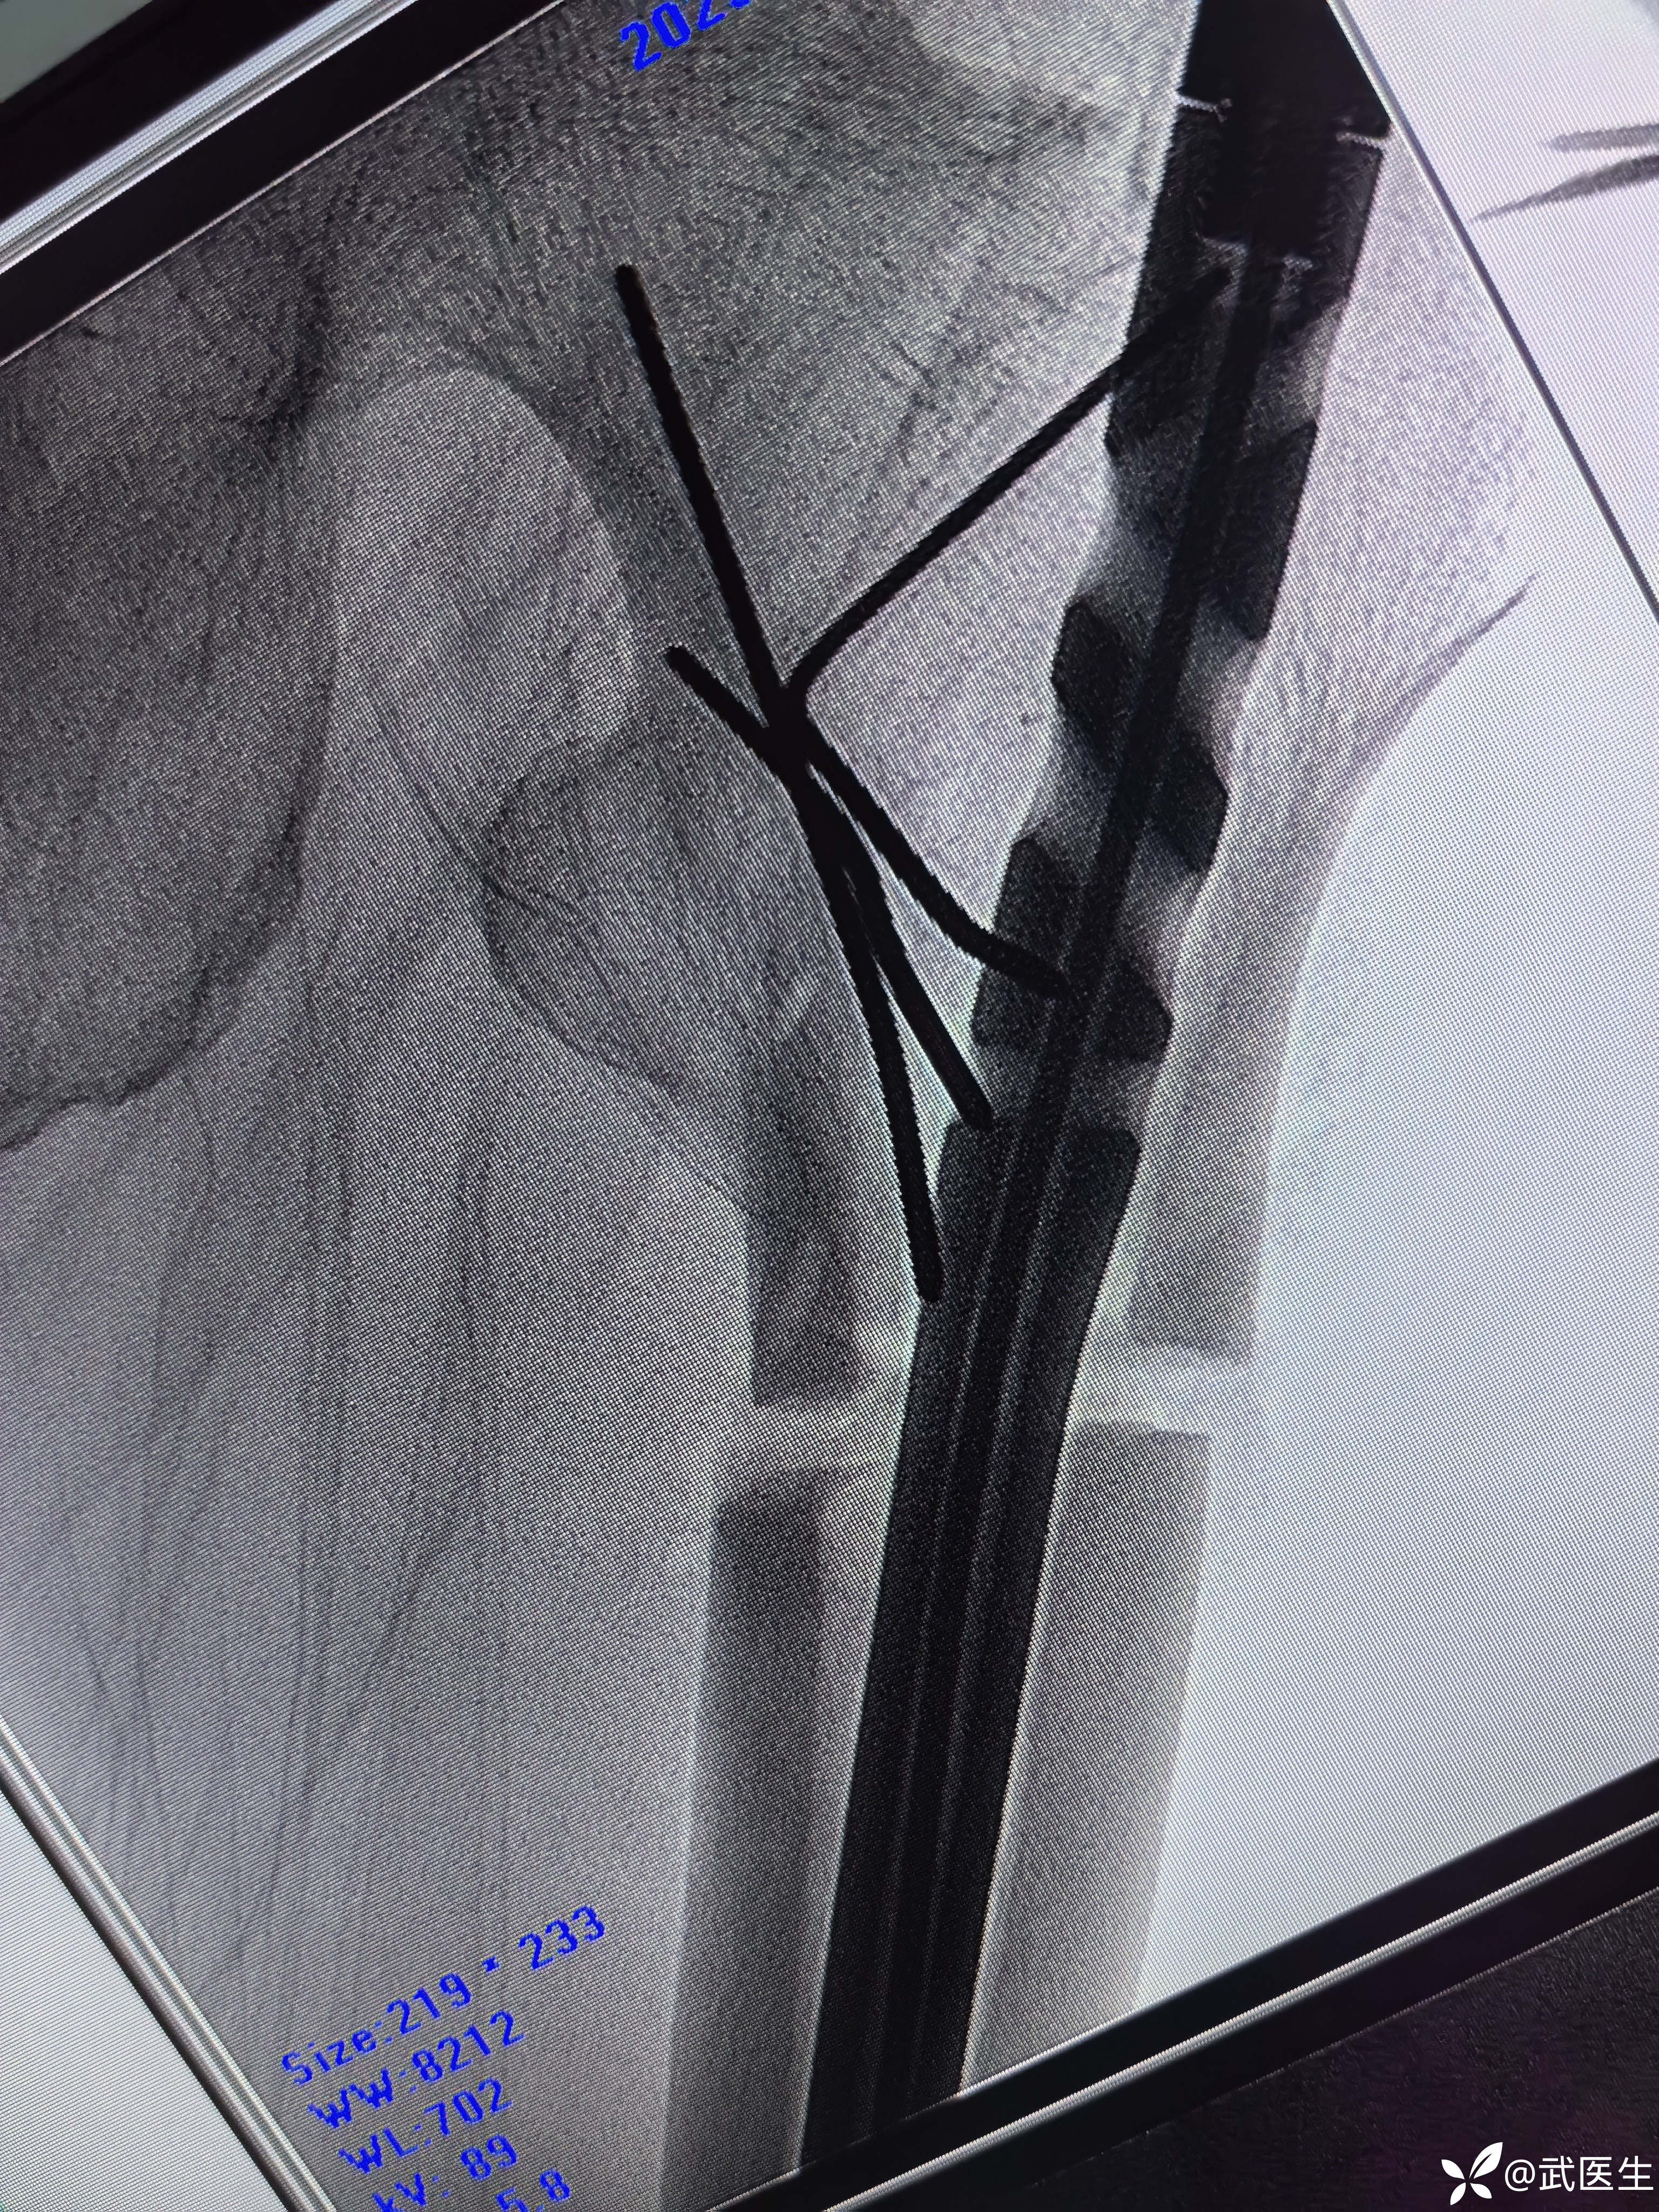

断端向外成角,对位不好,经常出现的问题,退出髓内钉,打阻挡克氏针,

置入

成角纠正,断端间隙有点大